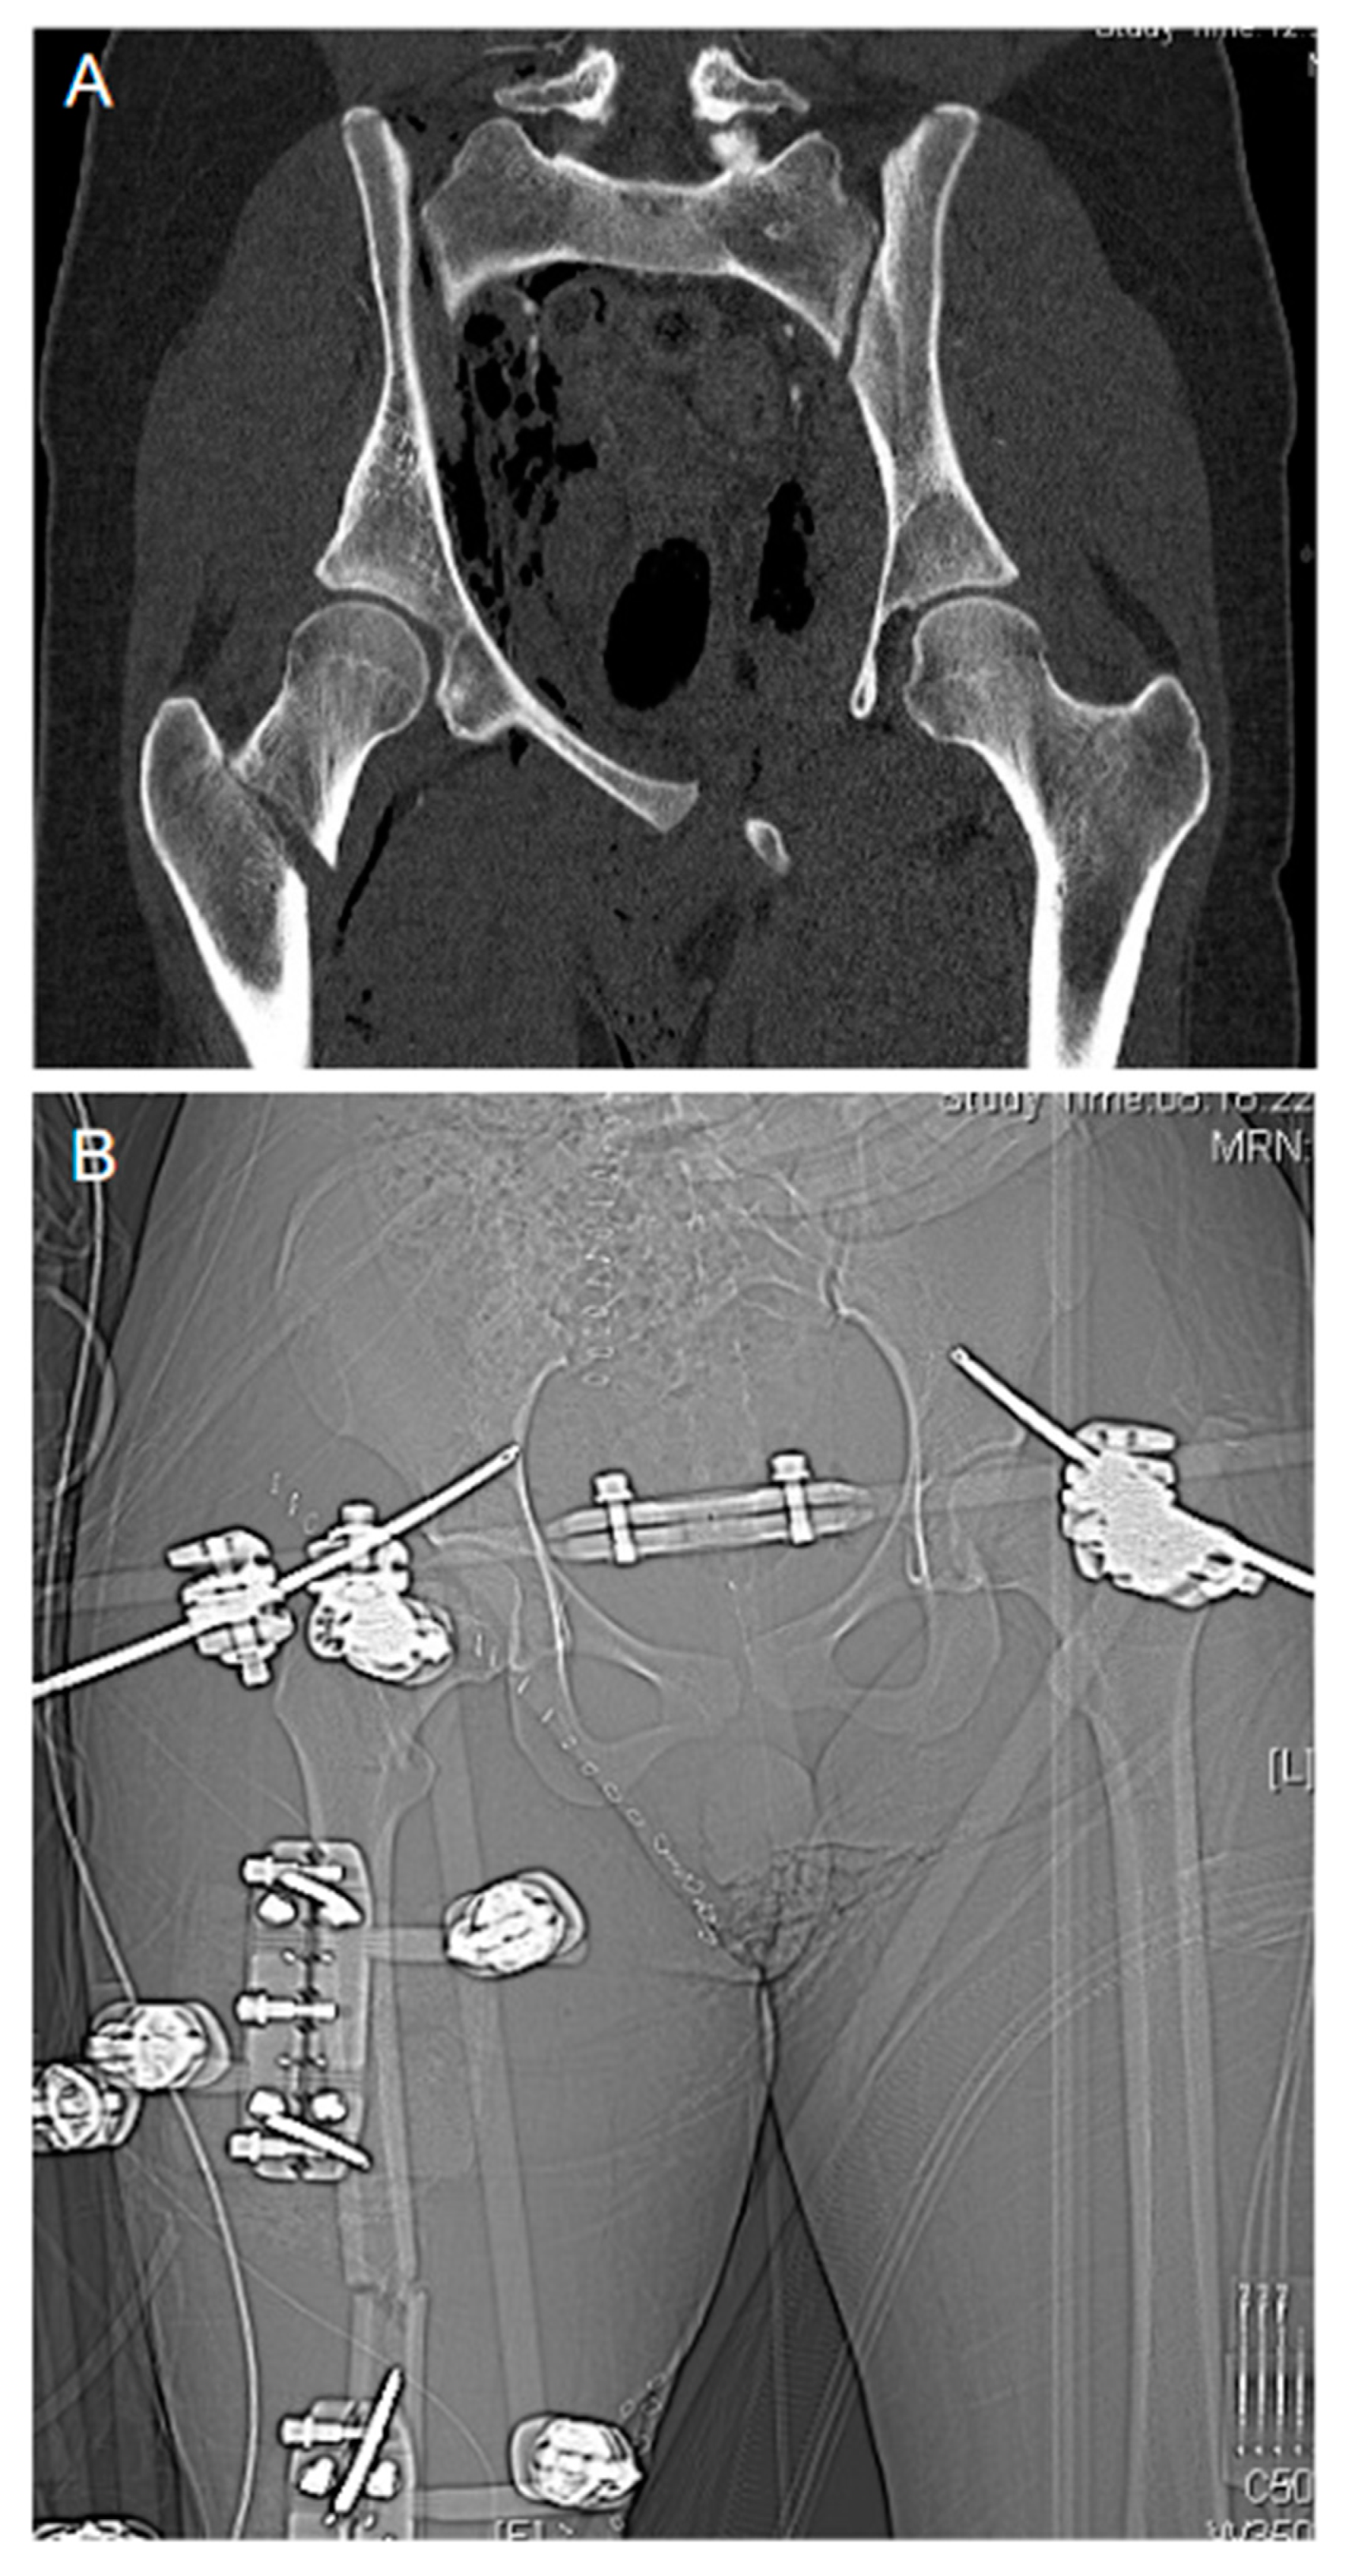

Figure 2. Damage control orthopedics. Emergency damage control orthopedics in a trauma case of combined displaced “open book” pelvic and right proximal femur fracture before (A) and after external fixation (B).

At hospital admission, the severity of the bleeding is estimated through a combination of the patient’s physiology, the anatomical injury and the trauma mechanism sustained (R4/1C). The Advanced Trauma Life Support (ATLS) classification of hemorrhagic shock has recently been questioned in its validity [30] and, as consequence, has been upgraded by the incorporation of the base deficit (BD) as an additional prognostic parameter in their latest version [31,32]. In the context of “permissive hypotension”, the bolus response to the administration of a defined fluid challenge is considered more and more critically (R13/1B). The role of imaging to detect free fluids in the thoracic and abdominal cavities as well as to identify and locate bleeding sources remains highlighted (FAST ultrasound [R7/1C], contrast-enhanced whole-body computed tomography [R7/1B]). Patients in which the bleeding source can be identified and those in severe hemorrhagic shock and with a suspected bleeding source are taken straight to the operation theatre for rapid bleeding control (R5/1C) according to the classical damage control procedures (R18/1B) with closure/stabilization of the pelvic ring (R19/1B) and abdominal packing (R20/1B; Figure 2). If there is an infrastructure given, angiographic embolization may be an option (R20/1B); in extremis and to gain time in life-threatening pelvic bleeding, retrograde endovascular balloon occlusion of the aorta (REBOA) may be considered until definitive care can be provided (R20/2C).